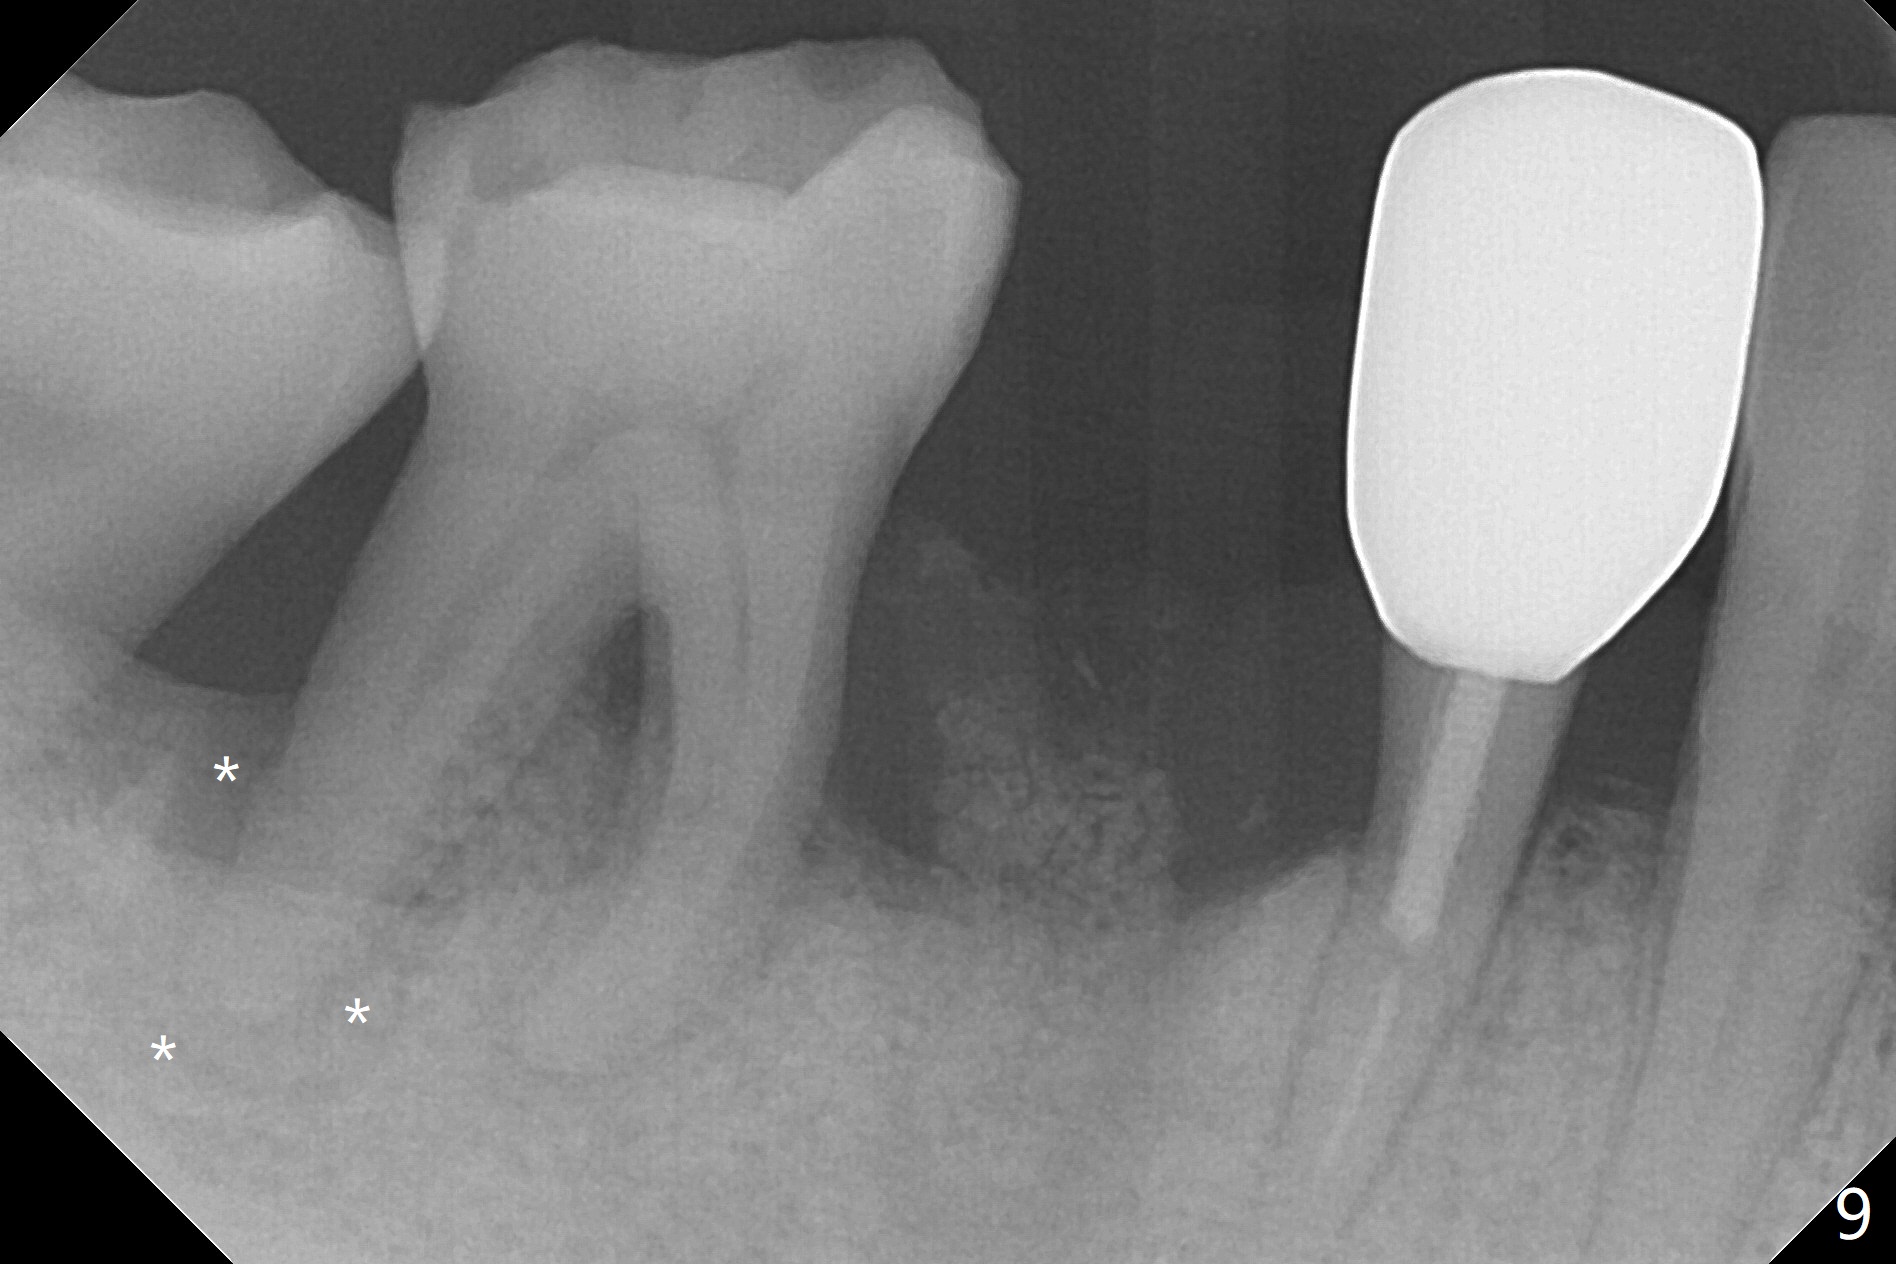

The tooth #29 is easily extracted with granulation tissue attached to the apex (Fig.1,2). The buccal plate is low. Initial osteotomy is established in the mesial slope of the socket for 13 mm subgingival (Fig.3 red dashed line). After adjustment of the osteotomy position and use of Magic Drills 2.8 and 3.3 mm for 15 mm subgingival, a 4x9 mm dummy implant is placed 2 mm subgingival (Fig.4). Final implant (Fig.5: 4x9 mm; red dashed line: socket) is placed 4 mm subgingival (supracrestal buccal; infracrestal lingual); Vanilla graft placed buccodistal (*). With placement of a 4.5x5.7(4) mm abutment (Fig.5), an infraocclusal immediate provisional (Fig.6 P) is fabricated to maintain the interdental papillae. One month later, the abutment dislodges. The patient insists upon no provisional so that he can masticate on the right side, since there is no functional molars on the left side. The implant appears to have osteointegrated 5 months postop (Fig7). The crown is loose 2.5 months post cementation (8.5 months postop); there is bone loss around the implant (Fig.8 *). Vanilla graft is placed after implant removal (Fig.9); in fact the neighboring teeth also have mobility (including periapical radiolucency at #30 (Fig.9 *)).